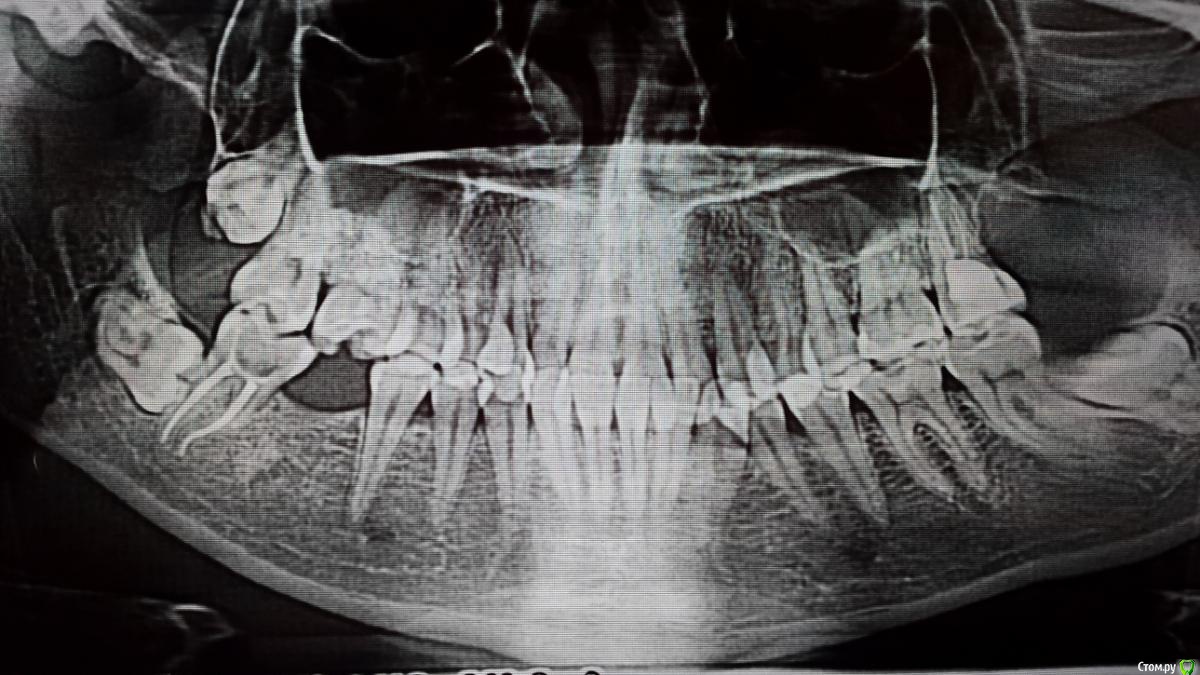

Tesh Опубликовано 13 декабря, 2018 Автор Поделиться Опубликовано 13 декабря, 2018 Всем доброго вечера!По рекомендациям доктора прошла всех специалистов (ЛОР, невролог, другие стоматологи), для исключения гайморита, камней, неврологии, пульпита. К сожалению, причин так и не нашли и ситуация остается острой, периодически боли усиливаются(Поэтому, уважаемые Доктора, прошу еще раз вглянуть на последний панорамный снимок, может все-таки кто-то увидит что-то.. (в конце снимка меня ударило по голове частью аппарата, поэтому смазано Ссылка на комментарий

DmitrySH Опубликовано 13 декабря, 2018 Поделиться Опубликовано 13 декабря, 2018 1. На КТ надо нормально посмотреть зуб 27. По этим снимкам мне он не очень нравится2. Убрать 38 Ссылка на комментарий